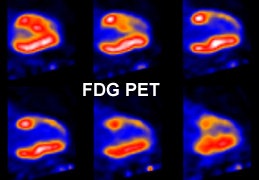

|

Myocardial scar: The patient below was being considered for coronary bypass surgery. A rest thallium exam demonstrated findings consistent with an apical and anterior wall scar. FDG PET imaging was requested to confirm that the patient was not a surgical candidate. The PET scan demonstrated a severe apical and anterior wall metabolic defect with less than 50% of peak myocardial activity corresponding to the thallium scan abnormality. The finding was consistent with prior apical and anterior wall infarct. |

|

|